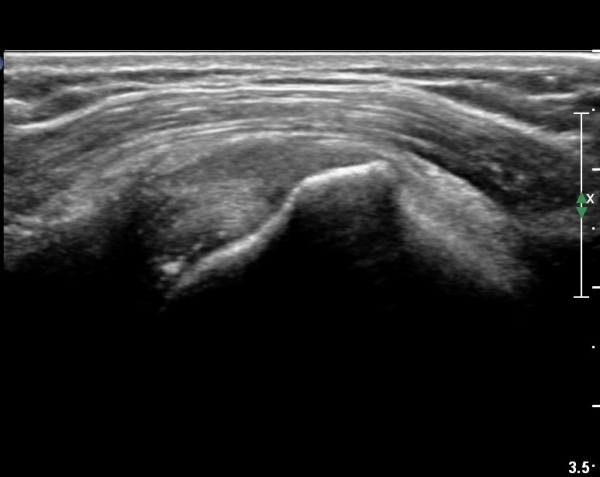

ȸÀü±Ù°³°£°Ý(rotator cuff interval) Ⱦ´Ü¸é°Ë»ç¿¡¼­ Á¡¾×³¶ÀÇ ºÎÁ¾ÀÌ °üÂûµÈ´Ù(»çÁø 3).